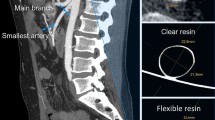

The CT acquisition of the phantom was compared to the original patient CT dataset from which the phantom was derived (Fig. 3). Three different radiological planes, at similar slices, are demonstrated; axial (Fig. 3a, b), Sagittal (Fig. 3c, d) and coronal (Fig. 3e, f). In both acquisition sets, there is contrast clearly visible within the vascular structures, allowing for delimitation from surrounding material. The aneurysmal sac of the complex abdominal aortic aneurysm (AAA) is seen in two orthogonal views (Fig. 3d, f), with orientation of visceral side branches, such as Iliacs (IL), Renals (RR/LR), Superior Mesenteric (SMA) and Coeliac (C), preserved. The PLA spine (S) included in the phantom model is visible as a radiopaque structure (Fig. 3b) and corresponds with the appearance of the spine from the patient’s CT scan (Fig. 3a).

Comparison of CT acquisitions from both the patient with an abdominal aortic aneurysm and the patient-derived phantom model. (a) Axial view of patient CT at the level of the renal artery bifurcation with the left renal artery (LR), spine (S) and aorta (A) demonstrated; (b) Corresponding axial view from the phantom model CT demonstrating the same structures surrounded by tissue mimicking material (TMM); (c) Sagittal view of patient CT demonstrating abdominal aortic aneurysm (AAA) sac, coeliac artery (C), superior mesenteric artery (SMA) and iliac artery (IL); (d) Corresponding sagittal view from the phantom model CT; (e) Coronal view of patient CT demonstrating the abdominal aortic aneurysm (AAA) and right renal artery (RR); f) Corresponding coronal slice of phantom model CT

The smallest vessel size fabricated in this model was the right renal artery (ca. 5 mm diameter); however depending on the resolution of the 3D printer system used, it may be possible to include vessels as small as 1 mm in diameter [21]. This would allow reproduction of complex arteriole vascular beds, such as those seen with arterio-venous malformations [22] if a good luminal model could be created. Indeed, the utility of dissolvable structures is not limited to recreation of vascular structures but can also potentially be used to simulate other hollow branching systems such as lymphatics, ureters or the biliary tree. Surrounding these structures with tissue mimicking material, cast in organ-specific shapes, could allow for realistic imaging phantoms for visceral organs such as the liver, kidney or prostate. The TMM used was specific to ultrasound imaging, however inclusion of alternative materials with differing imaging contrast could potentially allow for compatibility with further imaging modalities such as magnetic resonance imaging (MRI). Furthermore, the elastic properties of the tissue mimicking material used in this study can be altered by the addition of paraffin oil [17], allowing further tailoring of vascular phantoms for use with flow simulations in a wide range of clinical contexts [23, 24].